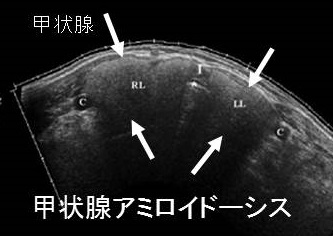

謎の結節性甲状腺アミロイドーシスを鹿児島大学が甲状腺学会で複数回、さらに大分大学も論文で報告しています。超音波(エコー)検査上、見かけは甲状腺腫瘍、境界不明瞭・不均質な低エコー領域で、石灰化も伴う。穿刺細胞診で腫瘍成分はなく、アミロイドのみが見つかるも、アミロイドーシスをおこす他の病気が全くないとの事です。

橋本病に合併した結節性甲状腺アミロイドーシスの病理組織標本では、

- アミロイド結節内の甲状腺濾胞構造は破壊され、異物反応や石灰化も存在する(第57回 日本甲状腺学会 P2-061 橋本病に合併した甲状腺amyloidosis の一例)

- アミロイド結節周囲の甲状腺組織には、リンパ球・形質細胞の炎症性細胞浸潤とリンパ濾胞形成を認めます。これらのリンパ球・形質細胞が、IgGのκ鎖を産生するのが原因では?と推察しますが、原因不明です。(第58回 日本甲状腺学会 P1-12-3 橋本病に合併した甲状腺限局免疫グロブリン軽鎖amyloidosisの一例)

- アミロイド沈着物は、細胞質内に小アミロイド滴を含む多数の組織球と多核巨細胞に囲まれる。しかし、血管壁にアミロイド沈着は無し。免疫組織化学検査により、アミロイドはアミロイドP成分、IgG、κ軽鎖が強陽性で、IgG、特にκ軽鎖(AL)が前駆体タンパク質と判明。[Acta Pathol Jpn. 1992 Mar;42(3):210-6.]。